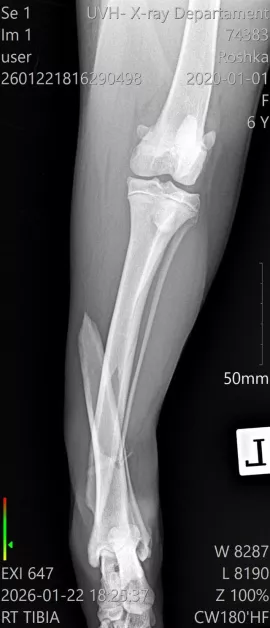

Диагнозата е тежка – две сериозни фрактури на задните крайници в областта на пищялите, с разместване и травмирани меки тъкани. По думите на ортопеда съществува реален шанс фрактурите да бъдат фиксирани с импланти и винтове, което би позволило на Рошка отново да проходи.